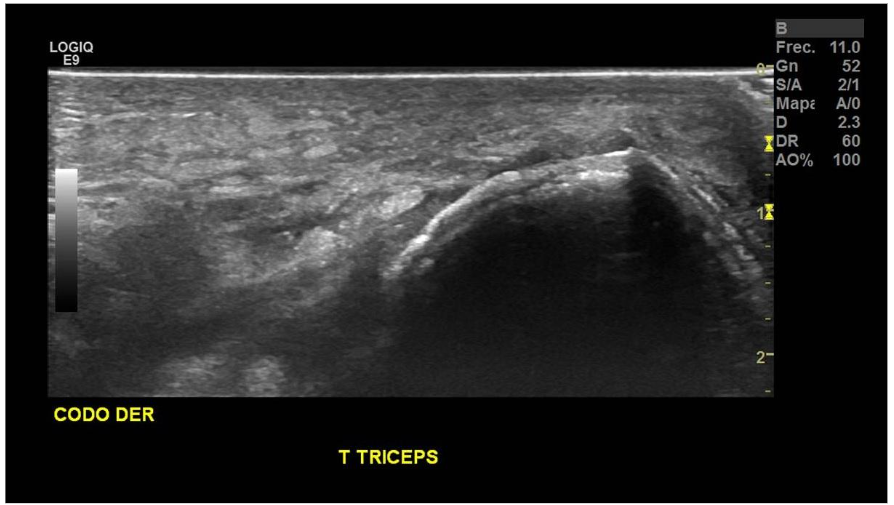

Paciente con antecedentes de fractura avulsiva del olecranon en codo derecho de 1 día de evolución, se presenta con hematoma y aumento de volumen difuso en articulación. Examen se solicita para conocer el porcentaje de compromiso del tendón tricipital.

Se observa retracción parcial de las fibras del TFC, sugerente de rotura parcial.

No se observan fibras del tendón del tríceps a nivel insercional, con fragmento óseo avulsivo en tercio medio del tendón del tríceps, correspondiente a rotura total.

Hallazgos: Tendón tricipital no visualizado en el tercio distal, en el contexto de rotura completa, con gap de 43 mm y fragmento óseo avulsivo en su espesor en el tercio medio, mide 9 mm. Se identificaron extensos cambios inflamatorios a este nivel y aumento de señal al estudio Doppler Color.